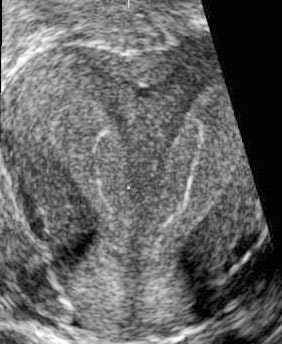

| Three-dimensional ultrasound images showing septate uteri. Images courtesy of Dr. Beryl Benacerraf. |

Foremost among these is the coronal view of the uterus, an only-in-3D image that can much more definitively distinguish the bicornuate from the septate from the unicornuate uterus.

"These kinds of images are incredibly important, particularly for the infertility patient," said Benacerraf, noting that women with septate uteri are at much higher risk for miscarriage, preterm labor, and other adverse effects.

With 3D, the sonographer can also measure the width and the depth of the septum, Benacerraf said, "which will be a very good guide for the surgeon who is going to be resecting the septum."